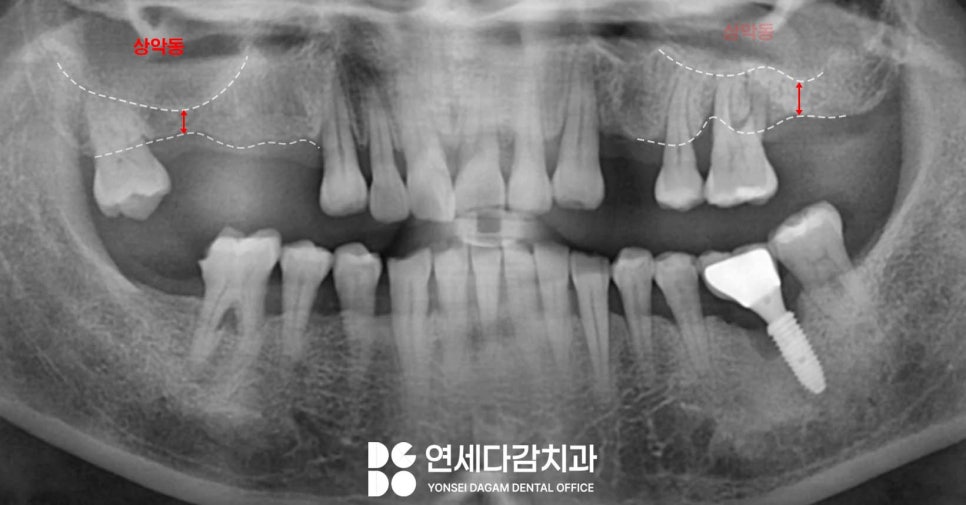

문정동 치과 에서 보여드리는

증례를 살펴보면

어금니 부위에 치아 결손이 존재하는

것을 알 수 있습니다.

위턱 어금니 부위에는

상악동이라는 구조물이

존재하기 때문에,

앞서 언급했던 것처럼

이러한 해부학적 구조물을

주의하여 수술을 시행해야 됩니다.

먼저 3차원적으로 구조를 파악할

수 있는 CT 촬영을 통해,

해부학적 구조물의 형태와 근접도,

잔존골의 높이와 폭을 분석하여

수술 계획을 수립합니다.

그 결과 문정동 치과 에서 표시한

부위를 살펴보면,

4mm 미만이었던 수직 골량이

8mm 정도로 증가하여

안정적인 골량이 확보되었습니다.